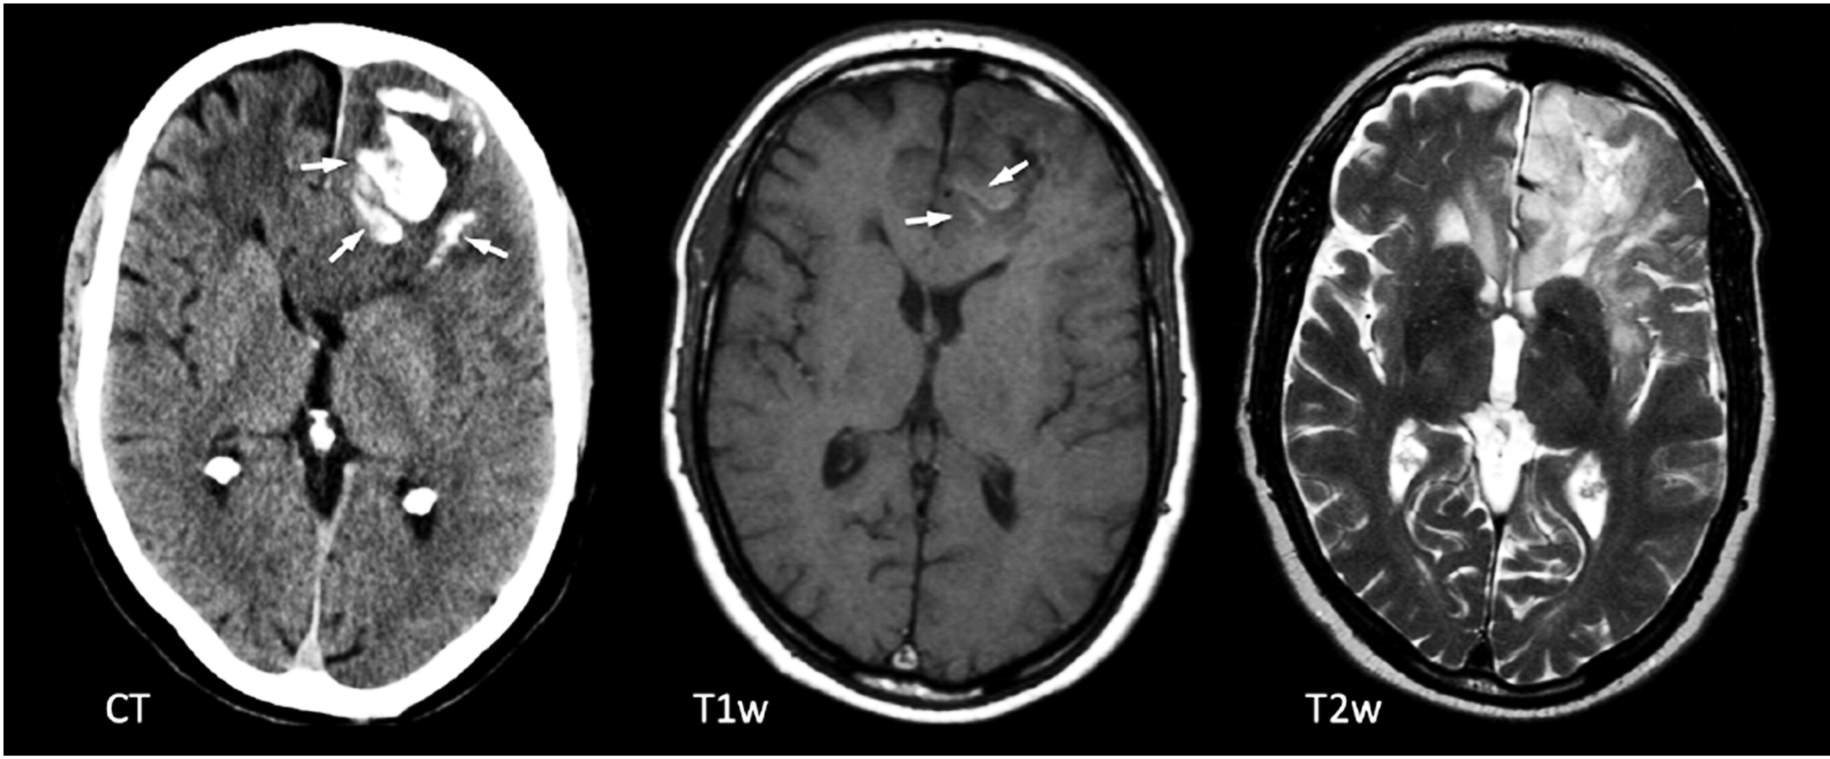

صورة 1: يُظهر الأشعة المقطعية (يسار) والتصوير بالرنين المغناطيسي (صورتان على اليمين) تكلسات (أسهم) على التصوير المقطعي في الفص الجبهي الأيسر، وهي سمة مُمَيِّزة جدًا للأورام الدبقية قليلة التغصُّن.

بعد دراسة التاريخ الشامل والفحص البدني، يمكن لتصوير الدماغ والحبل الشوكي تحديد الأورام المُحتملة. غالبًا ما يتم استخدام الأشعة المقطعية (CT) والتصوير بالرنين المغناطيسي (MRI) لتحديد حجم الورم وموقعه. تَستخدِم الأشعة المقطعية سلسلة من الأشعة السينية لإنشاء صورة مُتعدِّدة الأبعاد للدماغ. يَستخدِم التصوير بالرنين المغناطيسي المجالات المغناطيسية بدلاً من الإشعاع لإنشاء صورة مُماثلة للورم.